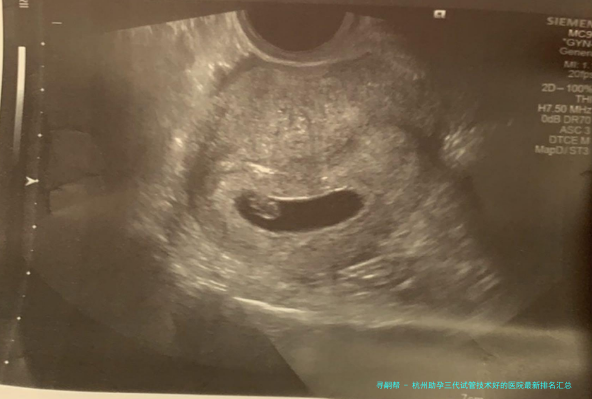

杭州优生医院配备了国际领先的助孕配备和设备,拥有出众的试管技术和配备。不论体外受精、胚胎移植还是其他辅助生育技术,该院均能提供高质量的服务。医院还时时引进国际前沿的试管技术和配备,维持技术层面上的领跑职位地方。

杭州优生医院的治疗效果备受肯定,很多患者在这里成功怀胎并顺当生育。医院享有一支富有经验的医疗团队,他们精湛的医术和耐心细密的服务为病人创造了良好的治疗成效。同时医院还注重治疗期间的沟通和交流,与病人建立起优秀的医患关联,强化了病人的治疗决心信念。